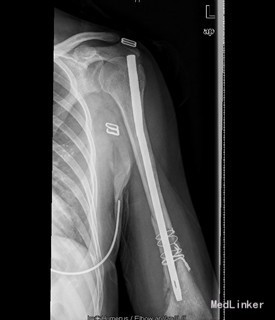

患者女,39岁,因“左肱骨骨折术后左肩关节左肘关节活动障碍6月”入院。 6月前患者外伤致左肱骨中下段粉碎性骨折,患者到当地人民医院行左肱骨骨折髓内钉及切开钢丝捆扎固定手术治疗(具体手术方式不详)。术后手术伤口恢复可,但患者左肩关节活动明显受限,并左肱骨下份肿胀严重,左肘关节活动稍受限。现患者左肩关节及左肘关节活动无明显好转,左上臂下段肿胀,皮温高。今患者到我院求进一步治疗。

查体:左上肢肱骨下段内侧有一10cm手术疤痕,下段肿胀,皮肤无明显发红。余四肢未见异常,活动无受限;左肱骨下份肿胀,未触及局限包块及波动感,肿胀区皮温高。桡动脉搏动正常。左肩关节活动明显受限,外展约20度,前伸后屈约20度,内外旋约15度,肘关节伸0度、屈45度。余关节活动无异常。 辅查:X片示左肱骨中下段骨折术后,内固定在位。

初步诊断:1、左肱骨骨折术后骨不愈合。2、左肩、左肘关节活动障碍 诊疗计划:择期行左肱骨髓内钉取出术、左肱骨骨折钢板螺钉内固定术,人工骨植骨。

术中见肱骨下份原骨折处软组织肿胀,瘢痕形成较多,有少量骨痂生成,能见原骨折端。取出髓内钉及固定钢丝后,骨折明显不稳定有假关节活动。未见明显炎性增生、渗出及坏死组织。并取随内及骨折周围部分组织送病检及培养。